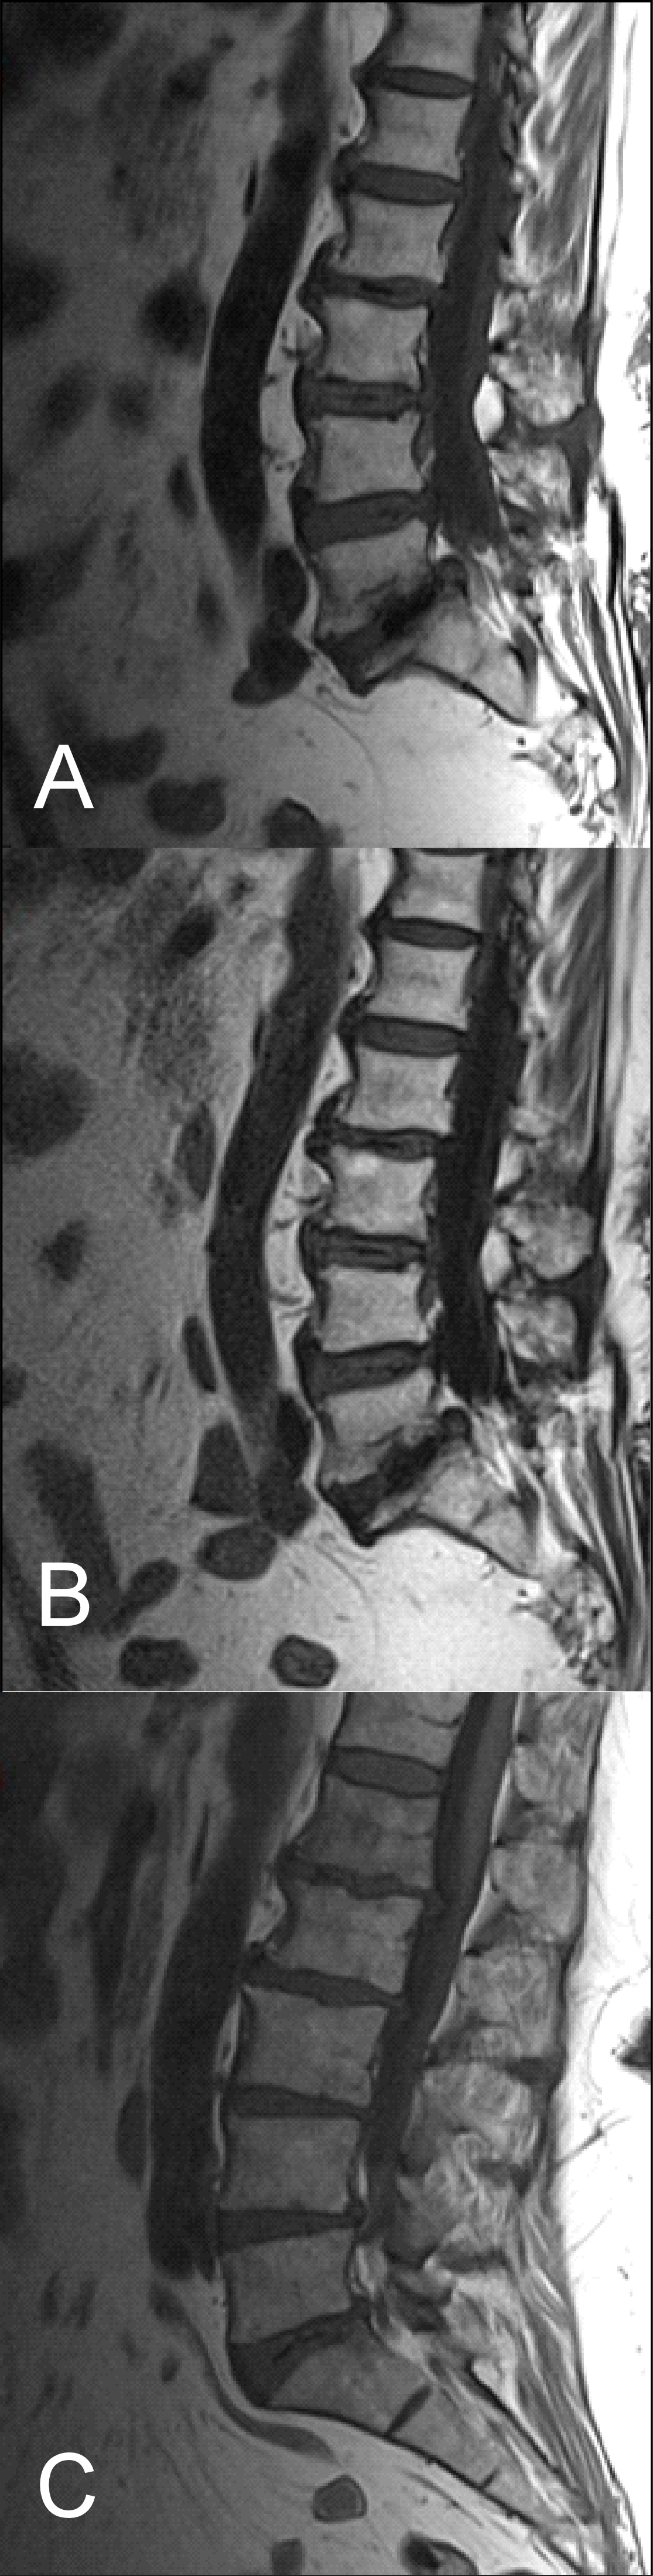

Although there have been many technical advances in MRI since it was first established, MRI of the L-spine is still challenging [14]. Unfortunately, there is a high chance of artifacts that can decrease the image quality, such as flow artifacts or motion artifacts, along with ringing artifacts, even in cooperative patients. However, if the patient is not cooperative there is a further risk of physical motion which can add motion artifacts, thus compromising image quality even more [17]. It is worth mentioning that in our experience, there is no significant improvement with BLADE in image quality in the presence of metal artifacts. So far, the successful application of BLADE in MR imaging of the brain to control motion artifacts (Figure 1) has been seen in pediatric or non-cooperative patients. BLADE is also seen to reduce flow artifacts after contrast administration. Some advantages have also been reported from BLADE in abdominal imaging but there are not sufficient data for the application of BLADE in spinal imaging [18].

The results obtained from the quantitative analysis of this study showed that the SNR and CNR results were significantly greater for T1W-FLAIR BLADE. More specifically, T1W-FLAIR BLADE sequence achieved better CSF nulling and better contrast between spongy bone and intervertebral disc as well as between spongy bone and intervertebral disc with CSF (Figure 2). A study by Alibek et al., has also demonstrated the superiority in image contrast of T1W-FLAIR images showing that they achieve better lesion to background and grey to white matter CNR [19]. The inherent restrictions of parallel imaging, i.e., reduction of SNR and increased possibility for reconstruction artifacts, were confirmed in our findings where the images without parallel imaging had better SNR (Figure 3).